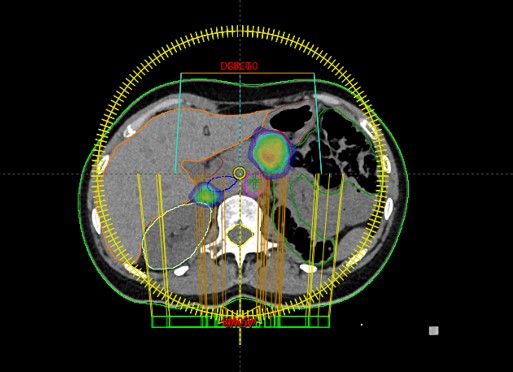

SBRT meta glandulae suprarenalis lateris dextri et pancreatis (08.11.-14.11.2018.)